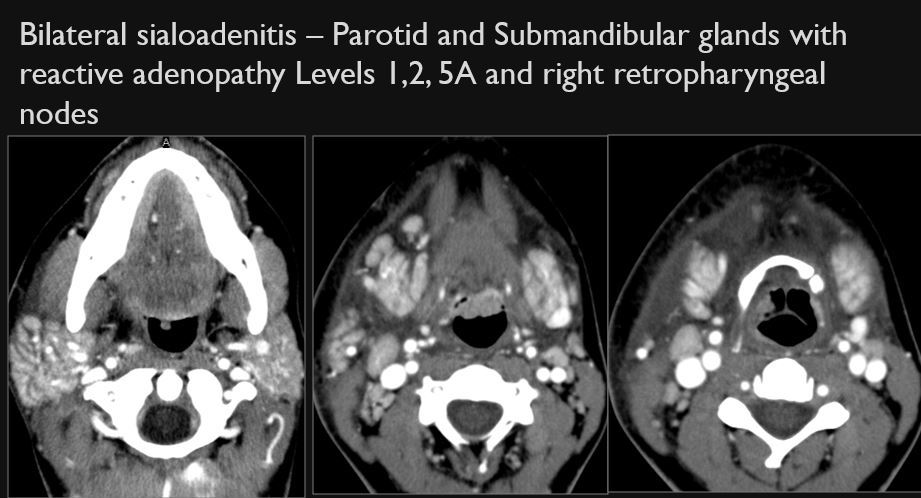

There is a developing abscess within the parotid gland.

The parotid ducts and/or intraglandular ductal systems are dilated and/or with evidence of intraductal stones other causes of obstruction.

There are intraglandular submandibular cysts and/or sialocoeles.

There is a developing abscess within the submandibular gland.

The submandibular ducts and/or intraglandular ductal systems are dilated and/or with evidence of intraductal stones other causes of obstruction.

The submandibular (Level 1) lymph nodes are abnormal by imaging criteria.

The other cervical (Levels 2-6), supraclavicular and/or retropharyngeal lymph nodes are abnormal by imaging criteria.